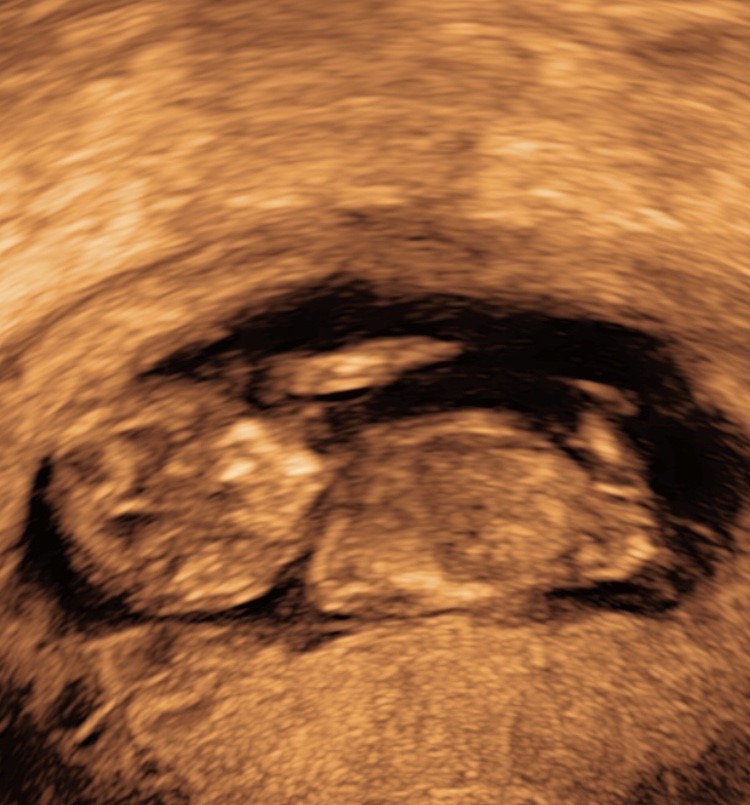

Jeg gætter pige! Nub’en kan fint ses og jeg syntes den ligger vandret lidt hældende nedad.